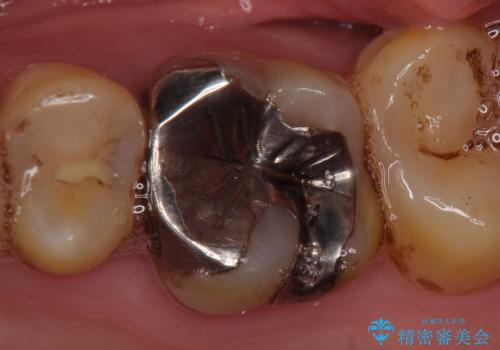

- ものを咬むと左上の奥歯が痛むので診て欲しいといらっしゃった方の症例です。

診査の結果、左上6が失活(歯の神経が死んでいる状態)しており根尖病変を認めたため、根管治療を行いました。

根尖病変の縮小及び症状の消失を確認後、オールセラミッククラウンによる補綴を行いました。